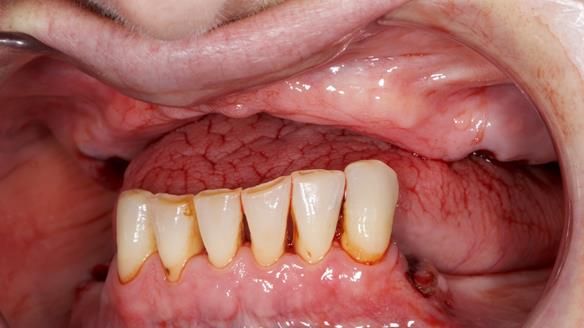

- The upper natural teeth have hopeless prognosis due to dental caries.

- The LR6, 5, 4 have guarded prognosis because of dental caries.

- The lower front teeth (LR3 – LL3) have better prognosis (although, I think there is high chance of loss – over the next 10 - 15 years). However, I do not believe it is right to remove them as they are in good condition compared with the other teeth and coping with a lower full denture is far more difficult (affecting your quality of life) than a lower metal based partial denture supported by natural teeth as proposed in the treatment plan below.

- The forces placed on the teeth are large (bruxism). This will make the dentures proposed in the treatment plan below wear, chip and break more quickly. Therefore, the final dentures will require metal reinforcement to make them as robust as possible.

- Upper complete denture and lower partial denture along with removal of failing teeth - Jo wanted this

The clinical situation and treatment process is shown in detail below. I provided the clinical work. Rowan Garstang provided the technical work. This treatment took 25 visits over a period of 12 months.